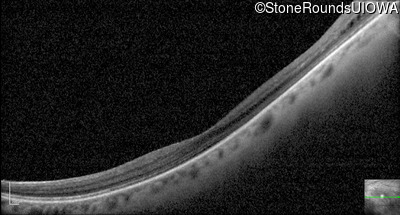

Optical Coherence Tomography - Left - 20/50 +3

Exemplar / OCT Stack

OCT Stack